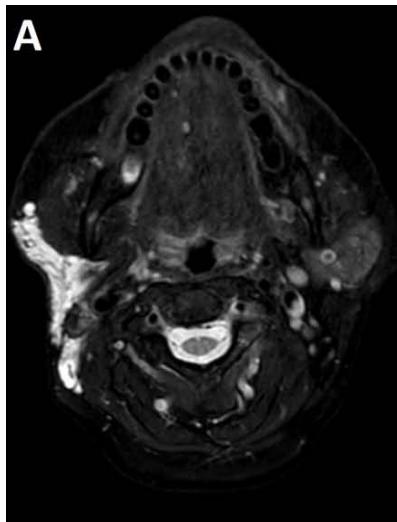

Histology is similar to hamartomas, although some state a lymphangiectasic or neoplastic nature, without any malignant potentiality [3]. Ultrasonography documents mono- or multiloculate fluid-superfluid lesions with a substantial lack of flow with Doppler mode (figure/patient 1-2). Computer Tomography (CT) describes low attenuation masses with occasional fluid level and minimum septal and peripheral enhancement. Magnetic resonance imaging (MRI) detects iso- or hyposignal on T1-weighted sequences and hyper-signal on T2-weighted sequences, a halo of enhancement around the septa of macro-cystic lesions and peri lesional lymphoedema (figure/patient 2-3) [4].